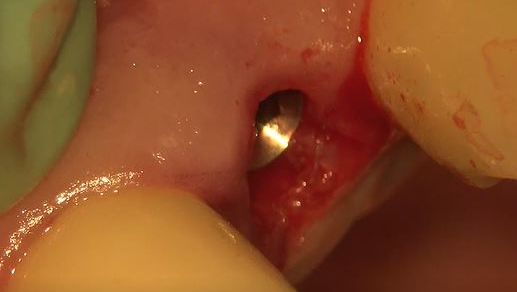

The decision to use the Ditron Implant System was based on the following treatment plan: extraction and immediate implant placement, with immediate provisionalization using a final titanium abutment. Extraction and immediate implant placement with immediate provisionalization have shown to be quite successful.

Maintaining initial stability is important when an implant is placed in a compromised extraction site, since there is less bone-to-implant contact there than in a healed site. Because of its architecture, the Ditron Ultimate implant offers a very high initial stability and strong abutment connection. The implant profile uniformly distributes the stress directly to the bone, which results in a more even distribution of force and lower long-term crestal resorption. This implant system has a good aggressive thread profile and a secure abutment connection, which are both key characteristics. The microthreads on the implant’s reverse conical neck (RCN) greatly increase the implant’s ability to resist axial displacement, and the mechanical stimulus the microthreads provide helps to preserve the peri-implant marginal bone. By inserting an Ultimate implant, 5.57 mm3 of bone will be saved compared to that of a non-RCN implant.7

First visit: Extraction and immediate implant placement, immediate placement of the final abutment prepared intraorally, and then a provisional out of function.